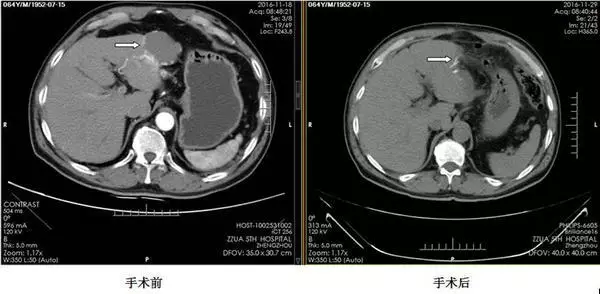

CT图像